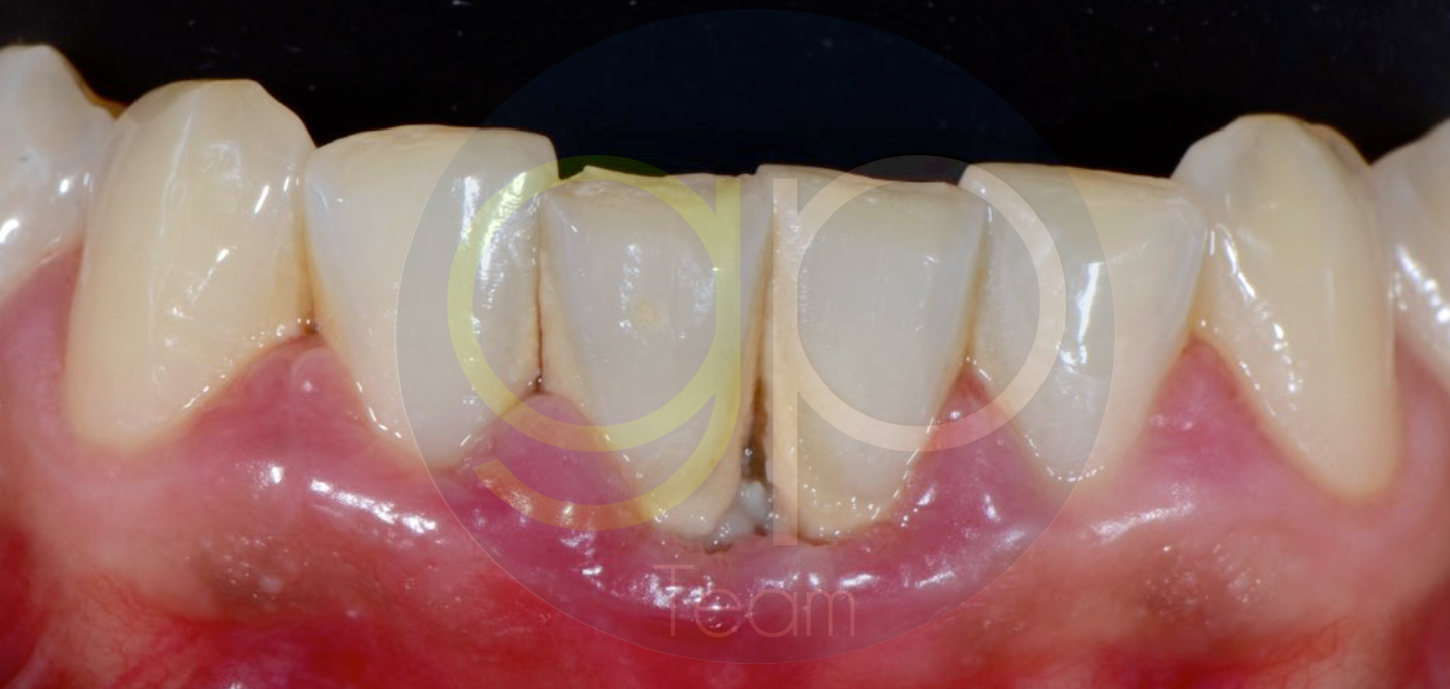

FIG. 4 : Guarigione ad 1 anno dei tessuti parodontali, trattati esclusivamente con terapia parodontale non chirurgica